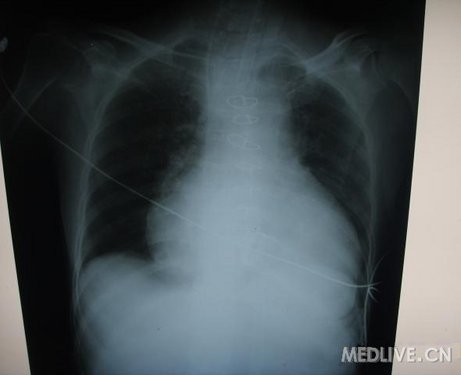

术后第2天,胸片提示心影较术后当天明显增大。

三尖瓣置换与二尖瓣置换术后监护明显不同,二尖瓣置换术后血压低多为左心功能不全,通过调节血管活性药物比较有效;但三尖瓣置换术后,血压低多为容量不足,增加血管活性药物效果多不明显,补充容量多有效。

这个患者就是补充了很多容量,血压才比较平稳的,因此心影增大。

http://webres.medlive.cn/upload/000/060/747